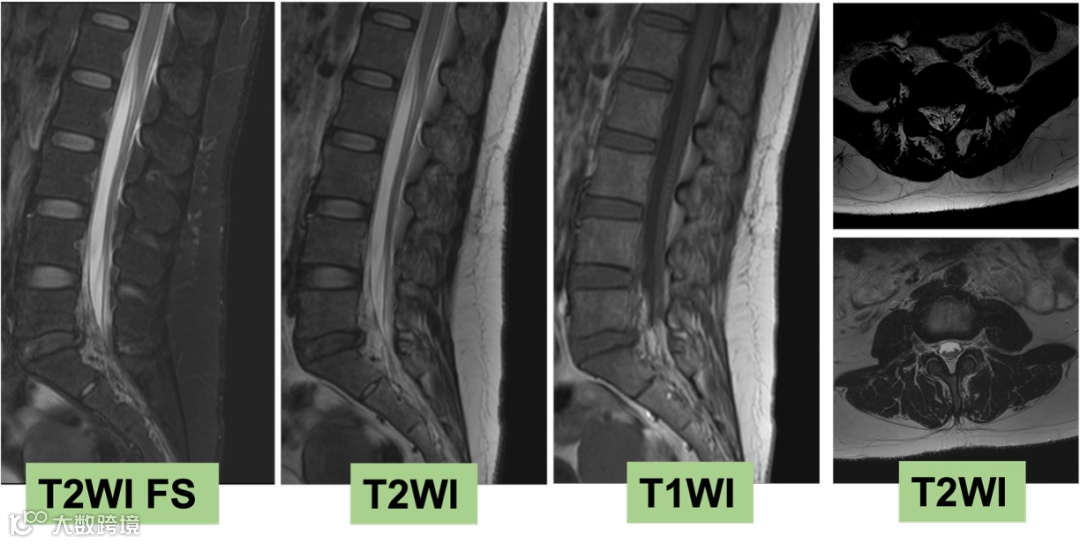

2025-07-14 颅脑MR平扫+增强+颈胸腰椎MR平扫

影像号:3462706

影像学表现